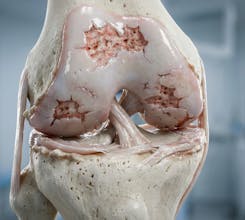

Natomy AI creates high-quality, medically accurate images and videos of human anatomy. Start with image-to-image: upload any low-quality photo, real image, or animation, and Natomy transforms it into an ultra-realistic anatomical visual. Unlike other AI tools that get anatomy wrong, Natomy is accurate every time—and fully editable by simply highlighting what you want changed and describing the update. Text-to-video launches in 2 weeks.